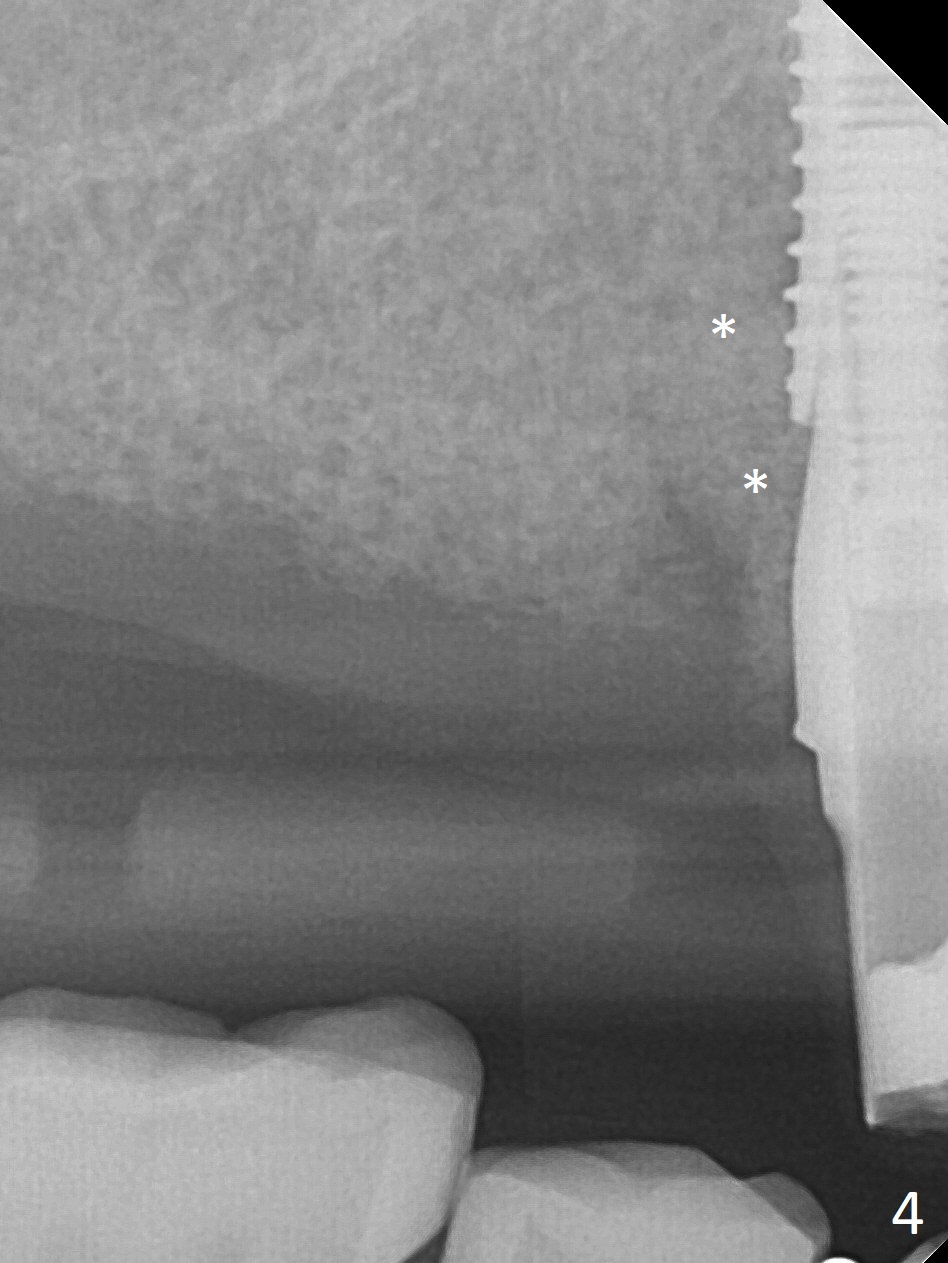

Extraction of the tooth #5 with mobility III reveals no buccal plate and low palatal plate.  Osteotomy starts as palatal as possible (Fig.1).  The bone density is low.  After use of 2.7 mm drill (Fig.2), a 3 mm drill can be inserted into the osteotomy without resistance.  A 4x16 mm implant is placed with insertion torque <30 Ncm.  When an abutment is placed, the implant is found to have been placed distal.   The implant is untorqued for change in trajectory.  When a 4.5x7(5) mm abutment is placed, the abutment turns with the underlying implant (Fig.3).  The former is kept to be turned with a hand driver until the latter is unable to turn.  Following placement of allograft (Fi.g3,4 *), a mini-provisional is fabricated to retain the bone graft and at the same time not to be interfered with when a flipper is in and out.  The bone graft in the former socket gap appears to have integrated into the native one 4.5 months postop (Fig.5).